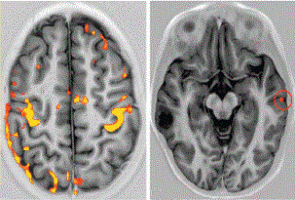

Using a drug called Safusidenib - an oral inhibitor targeting the mutated IDH1 gene – researchers from the Royal Melbourne Hospital (RMH), WEHI and the Peter MacCallum Cancer Centre (Peter Mac) observed the drug's effect on LGGs tumour samples both before and after treatment.

“For the first time, we’ve seen what a drug is doing in the brain with incredible detail, helping us to clearly identify the next steps for personalising treatment and predicting who would most benefit.”